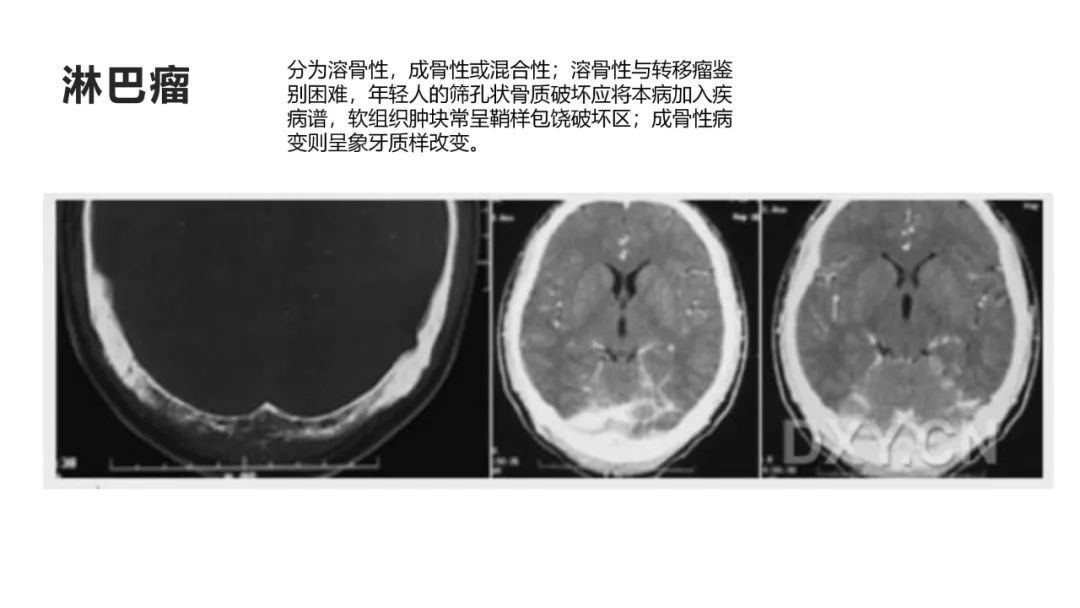

颅脑影像诊断基础知识讲座:颅骨病变